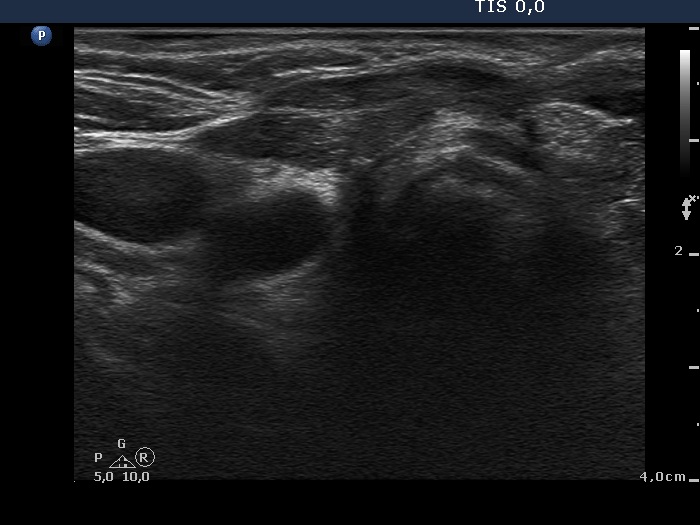

Eleven years after surgery (second and third rows of images):

Clinical data: The patient came to a follow-up. He told us that he decided not to visit the surgeon because the mass did not cause any complaints. He didn't remember exactly, but a few years ago he couldn't feel the knot at all, it had slowly disappeared on its own over the years.

Palpation: no abnormality.

Laboratory tests: TSH 3.56 mIU/L on daily 75 microgram levothyroxine.

Ultrasonography. The right lobe remained unchanged. Compared with the previous finding, a much smaller, inhomogeneous mass was found according to the left lobe. A few centimeters above and ventral to the left lobe, a cystic lesion was found within the strap muscle and close to this, an amorphous hyperechoic fragment was also present (see video).